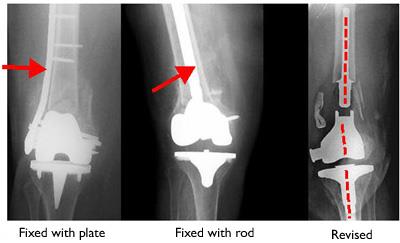

Internal fixation of distal femur fractures

Healed fractures treated with a plate (left) and a rod (right).

There is also the potential problem of distal femur fractures around existing knee replacements. As the population ages and the number of knee replacements rises, more distal femur fractures are being seen in those with knee replacements.

Distal femur fracture near an artificial knee joint

These X-rays taken from the front (left) and the side (right) show a fracture near an artificial knee joint.

Fractures around knee replacements are typically treated with rods or plates, just like other distal femur fractures.

In rare cases, the existing knee replacement must be removed and replaced with a larger replacement. This procedure is called a revision and may be necessary if the implant is loose or not supported by surrounding healthy bone.

Fractures near artificial knee joint treated with internal fixation and revision knee replacement

Fractures near knee implants may be treated with plates, rods, or with a revision surgery.